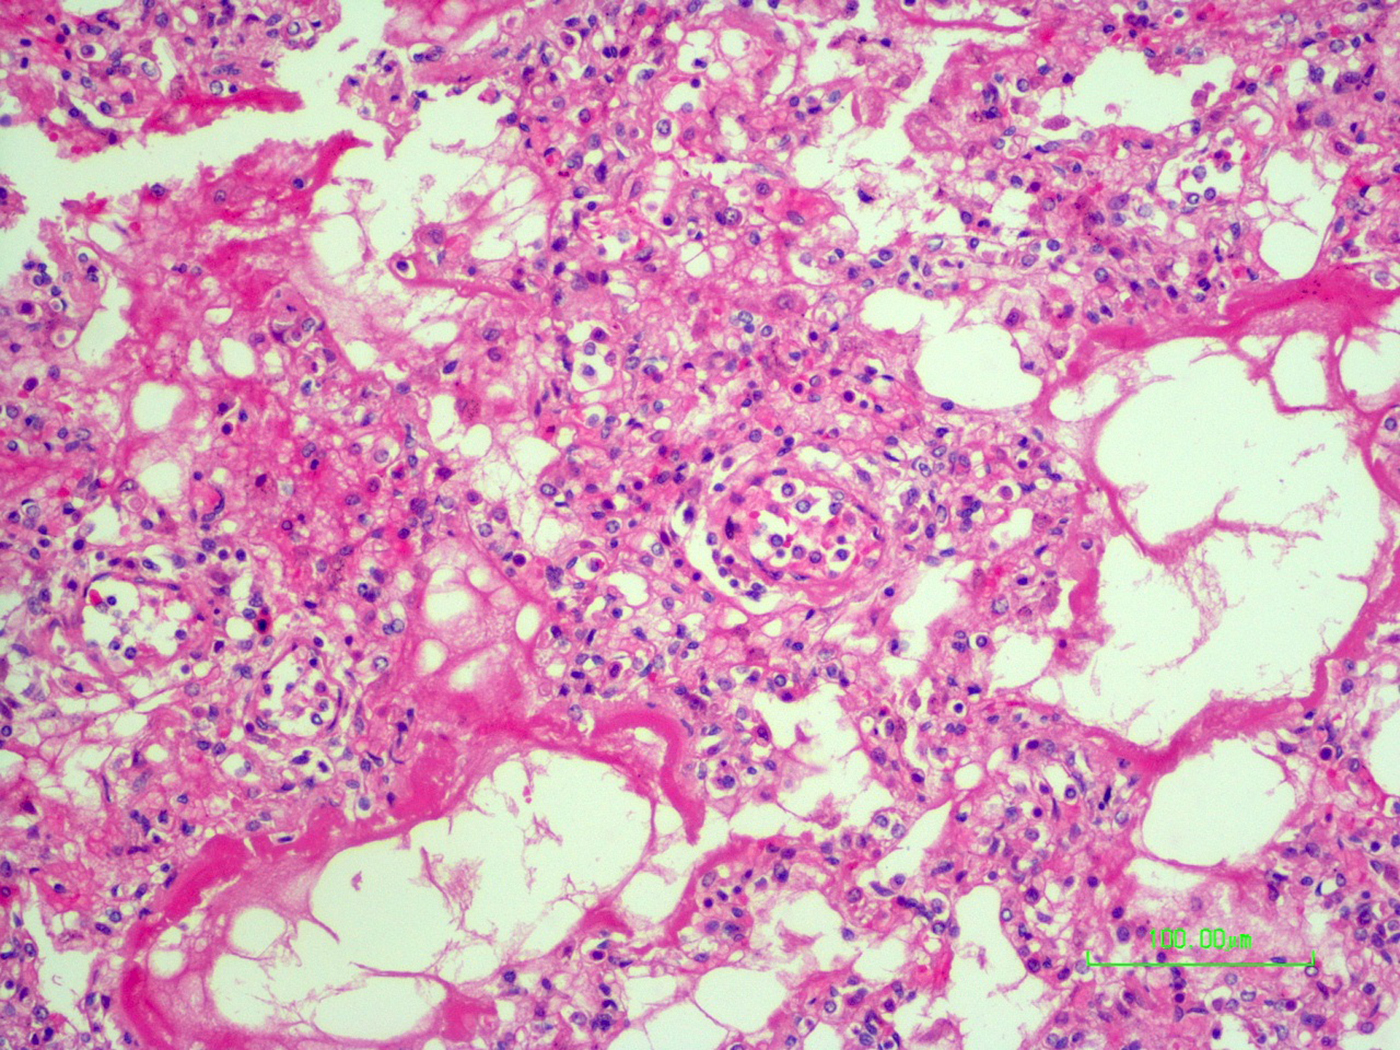

The autopsy revealed petechiae and generalised oedema (Fig. 1), congestion and focal haemorrhage in multiple organs associated with generalised vasculopathy of small-medium vessels with partial fibrin microthrombi formation, pericardial, pleural and peritoneal effusion, and interstitial pneumonitis with diffuse alveolar damage (Fig. 2). Additionally, the patient had foci of endo-myocarditis, acute renal tubular necrosis and chronic hepatitis.

Fig. 2. Interstitial pneumonitis and diffuse alveolar damage (HE 100×).